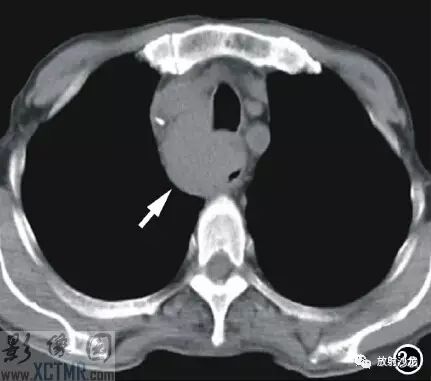

上消化道鋇餐:食管胸上段可見不規則充盈缺損,約5.6cm*4.2cm,黏膜結構紊亂,管壁不規整,對比劑通過稍緩慢,會厭動度不協調,考慮食管癌(圖2)。CT:食管胸上段見軟組織腫塊,上自杓會厭披裂,下至主動脈弓水平,腫塊邊緣清晰,密度均勻,增強掃描輕到中度不均勻強化,食管腔狹窄,氣管、右側甲狀腺、鄰近血管受壓移位(圖3),縱隔未見腫大淋巴結,診斷:食管癌可能。